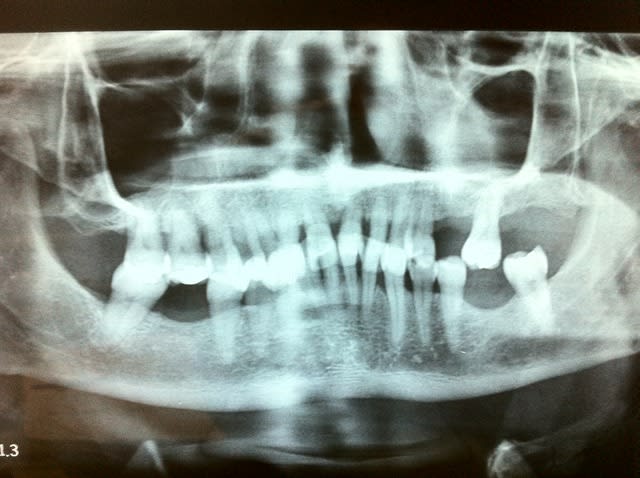

Faut pas pousser. Ce matin patient RDV 11h30 et sorti 12H05, Status radio (on ne sait jamais pas venu depuis 2009) endo, empreinte, provisoire incluses. Un peu énervé par le lapin d'une heure plus tot dans la matinée !

Blague en coin: viens de passer près d'une heure à tchatcher avec un artisan, plan de traitement de ouf, on sait pas où on va, ni combien de temps ça prendra ni combien ça coutera mais je sais qu'il a compris que son cas est complexe, sera long et surtout que mes honoraires seront justifiés.

1/ retrouver une dv par gouttiere ou pistes directes, la tester sur x mois

2/ ortho et paro, x mois aussi

3/ implanto

4/ protheses

Ouais mais vu la rétraction pulpaire une reconstitution pré endo aurait quelque peu obscurci le champ opératoire, je rase pour y voir plus clair.